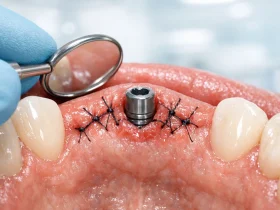

بخیه ایمپلنت دندان چیست؟بخیه ایمپلنت دندان یکی از مراحل مهم پس از جراحی ایمپلنت است که برای ...